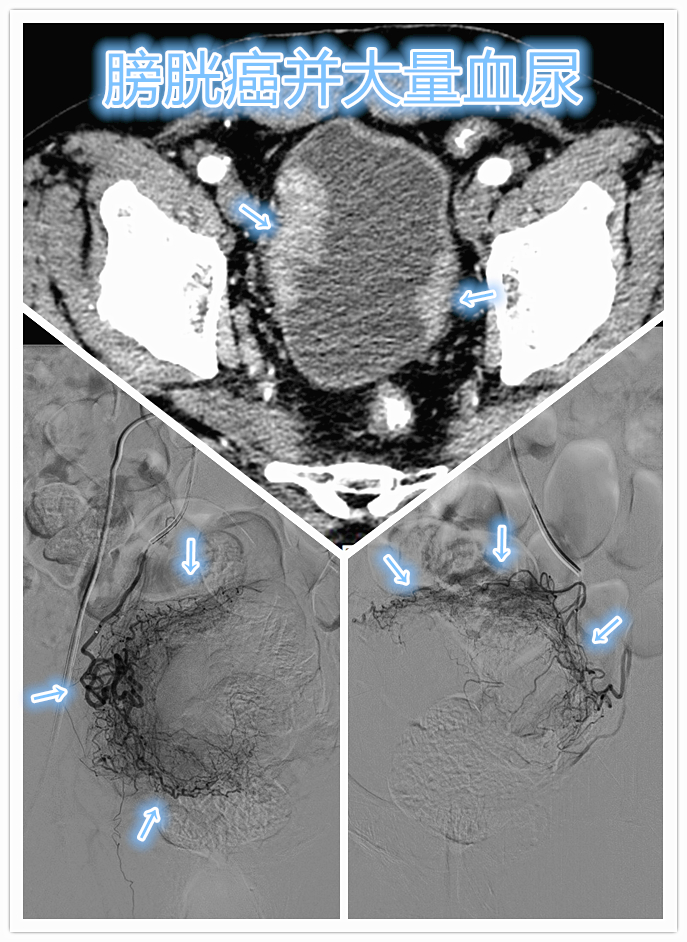

肿瘤内科急请会诊,原来是位高龄膀胱癌患者出现大量血尿,老陈经药物止血无改善,已经输注浓缩红细胞4单位,监测血红蛋白(56g/L)仍无明显改善,提示内科药物止血治疗已无效。老陈因严重贫血,已经出现活动后胸闷、心悸、头晕等贫血症状。查阅患者近期增强CT检查,显示膀胱壁明显增厚,可见多发肿瘤突向膀胱内,考虑患者大量血尿系膀胱肿瘤溃破出血所致。#头条健康# #非常病例#

在详细解释告知介入微创手术相关风险性及疗效后,老陈患者家属签字同意介入治疗。随即介入科紧急安排急诊手术,术中DSA血管造影显示双侧膀胱动脉明显增粗、迂曲,肿瘤染色丰富,采用顺铂与明胶海绵细颗粒充分混悬制备而成的栓塞剂,行双侧膀胱动脉化疗栓塞,一方面可以有效快速止血,另一方面加载的化疗药物可以对肿瘤细胞*伤杀**作用,控制肿瘤、减少术后再次大出血可能。

CT显示膀胱壁明显增厚,膀胱壁肿瘤广泛侵袭;DSA造影显示双侧膀胱动脉明显增粗、迂曲,肿瘤染色丰富。